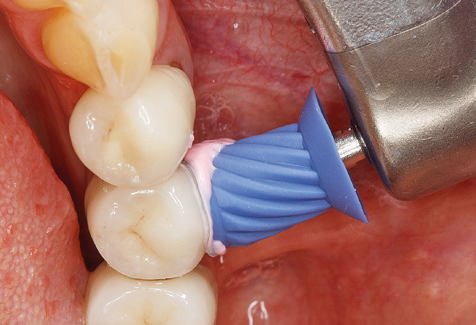

Die gute Ausleuchtung des Arbeitsfeldes stellt eine wesentliche Erleichterung dar. Bei dem von den Autoren genutzten System ist dies gelungen, indem ein 5­facher LED­Ring in das Handstück integriert wurde. Natürlich werden für dieses System unterschiedliche Arbeitsspitzen für die jeweiligen Indikationsbereiche angeboten. Eine gerade, universell einsetzbare Spitze ist das Basisinstrument zur maschinellen Instrumentierung natürlicher Zähne (Abb. 5a und b). Für schwer zugängliche Bereiche im Seitenzahnbereich werden gebogene Spitzen angeboten, die auch einen Zugang zu freiliegenden Furkationen ermöglichen (Abb. 6).

Unerlässlich für die UPT implantat­ prothetisch versorgter Patienten sind natürlich Arbeitsspitzen für die Reini­gung von Implantatoberflächen. Der Implantatreinigungsaufsatz des hier verwendeten Systems zeichnet sich dabei durch eine spitz zulaufende sechskantige konische Form aus. Dieses Design erlaubt ein leichtes atraumatisches Eindringen in die periimplantäre Tasche und zeigt eine gute Reinigungsleistung (Abb. 7).

Nach der maschinellen Reinigung der Zahn­ und Implantatoberflächen erfolgt eine manuelle Instrumentierung der natürlichen Zahnoberflächen mit konventionellen Handinstrumenten. Bei der manuellen Reinigung ist insbesondere auf einen korrekten Anstellwinkel, eine ausreichende Schärfe, eine gute Abstützung und auf eine von apikal nach koronal gerichtete Arbeitsweise der Kürette zu achten. Zur Nachinstrumentierung der Implantatkonstruktionen sollten entweder Titan­ oder Carbonküretten verwendet werden (Abb. 8). Ergänzend zum Einsatz von Ultraschallgeräten können in der Erhaltungstherapie auch Pulverstrahlgeräte genutzt werden. Dabei ist jedoch zu berücksichtigen, dass diese Verfahren nicht zum Entfernen harter Beläge geeignet sind und daher die Verwendung von Hand­ oder Ultraschallinstrumenten nicht komplett ersetzen können. Abschließend erfolgt in jedem Fall eine mechanische Politur der zugänglichen Zahn­ und Implantatoberflächen mit Polierkelchen und Polierpasten (Abb. 9).

Abb. 4: Für das Sondieren an dentalen Implantaten sind biegsame, millimeterskalierte Sonden empfehlenswert (z.B. Colorvue Kit PCV11KIT6, Hu-Friedy). – Abb. 5a und b: Eine gerade Arbeitsspitze (1P, W&H Dentalwerk Bürmoos GmbH) ist universell für die Instrumentierung natürlicher Zähne geeignet. – Abb. 6: Für die Bearbeitung schwer zugänglicher Bereiche der Zahn- und Wurzeloberflächen (z.B. Furkationen) bieten sich gebogene Arbeitsspitzen (3Pr/3Pl, W&H Dentalwerk Bürmoos GmbH) an. – Abb. 7: Die spitz zulaufende sechseckige Implantatreinigungsspitze (1I, W&H Dentalwerk Bürmoos GmbH) ermöglicht eine atraumatische und effiziente Reinigung der Kronen- und Abutmentoberflächen. – Abb. 8: Für die manuelle Instrumentierung der Implantatoberflächen sind Titan- oder Carbonküretten geeignet.